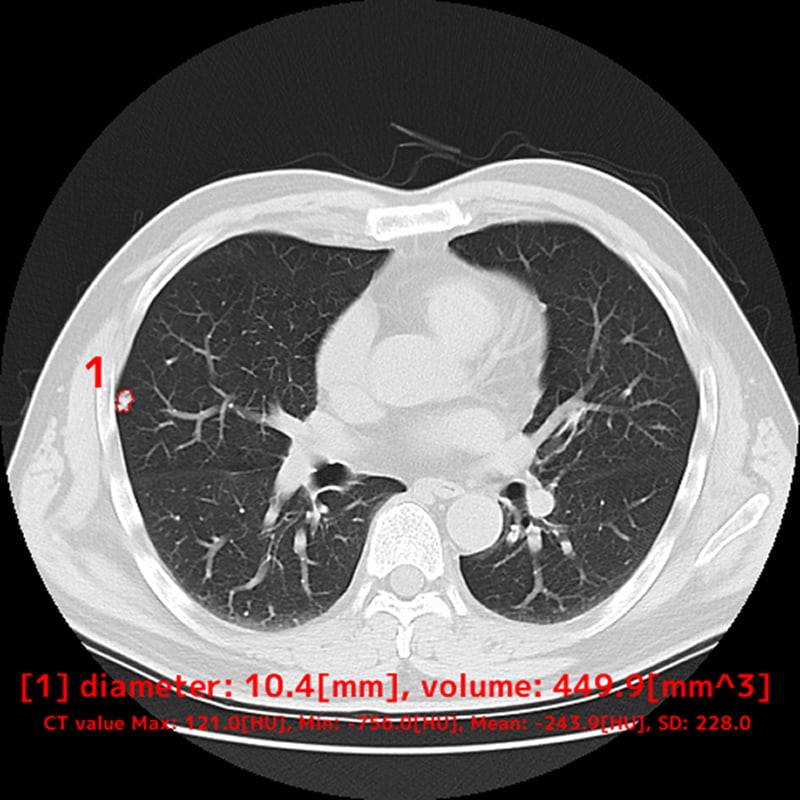

胸部CT画像から肺結節の候補領域を検出

胸部CT画像から肺野領域において、肺結節候補領を自動検出し、その体積と最大径を計測することで、医師の読影診断を支援するソフトウェアです。